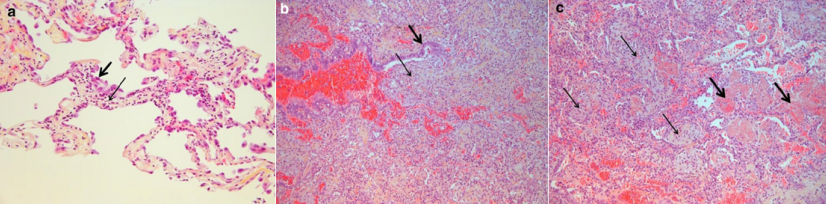

图片

注:a. 肺泡壁被大量淋巴细胞浸润和水肿(细箭头);b. 支气管内的松散结缔组织(细箭头);c. 肺泡管内的组织性肺炎(细箭头)与纤维蛋白球(粗箭头)共存。

图源:Intensive Care Med, 2020, 46(6):1124-1126.

2000年一项COVID-19患者的尸检报告发现,在6例死亡患者中有5例出现了机化性肺炎,在肺泡腔及细支气管中都填充着纤维素样渗出[19]此时增加PEEP并不会产生任何作用,相反,正常肺泡过度膨胀,患者气压伤和呼吸机相关性肺损伤的发生率显著增加。